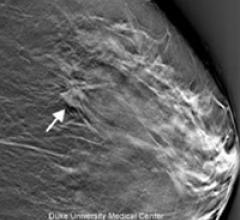

Despite decades of progress in breast imaging, one challenge continues to test even the most skilled radiologists ...